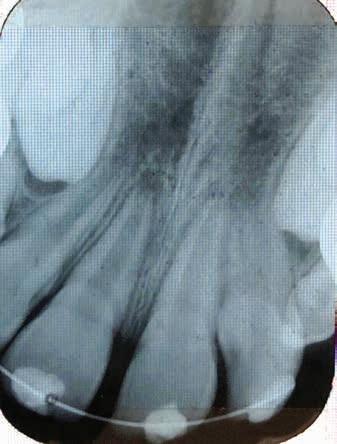

Intraoral assessment revealed that the maxillary left permanent central incisor was intruded 6-7 mm along with buccal displacement. No other extraoral, intraoral or dental injuries were noted. Intraoral radiographs taken confirmed the intrusive luxation injury. The permanent lateral incisors had erupted and the primary canines were not mobile. The initial clinical presentation of the child and associated radiograph are shown in Figure 1. Informed consent was obtained from the patient’s parents to initiate treatment.

Figure 1. Initial clinical presentation and radiograph of the child at approximately 30 minutes of the dental injury.